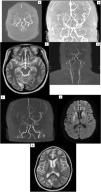

ResultsThere are 58,905 unique MRI scans from 2019 to 2023. The cohort comprises 8 females and 2 males, with a median age of 37 (7–65) years old. Three cases are probable MMD. with six MMD cases and one MMS case. Therefore, the prevalence rate for the four years is approximately 11.9 cases per 100,000 scans. Out of the confirmed Moya-Moya cases, the majority (4/7) are ischemic subtypes, followed by epileptic (electroencephalography shows slowing brain waves) and TIA in one case each. The most common presenting symptom is weakness in the extremity (N = 7), followed by headache (N = 5). Four patients underwent operative procedures, with three of them being superior temporal artery to middle cerebral artery (STA-MCA) bypass procedures and one of them being encephalo-duro-myo-arterio-pericraniosynangiosis (EDMAPS).